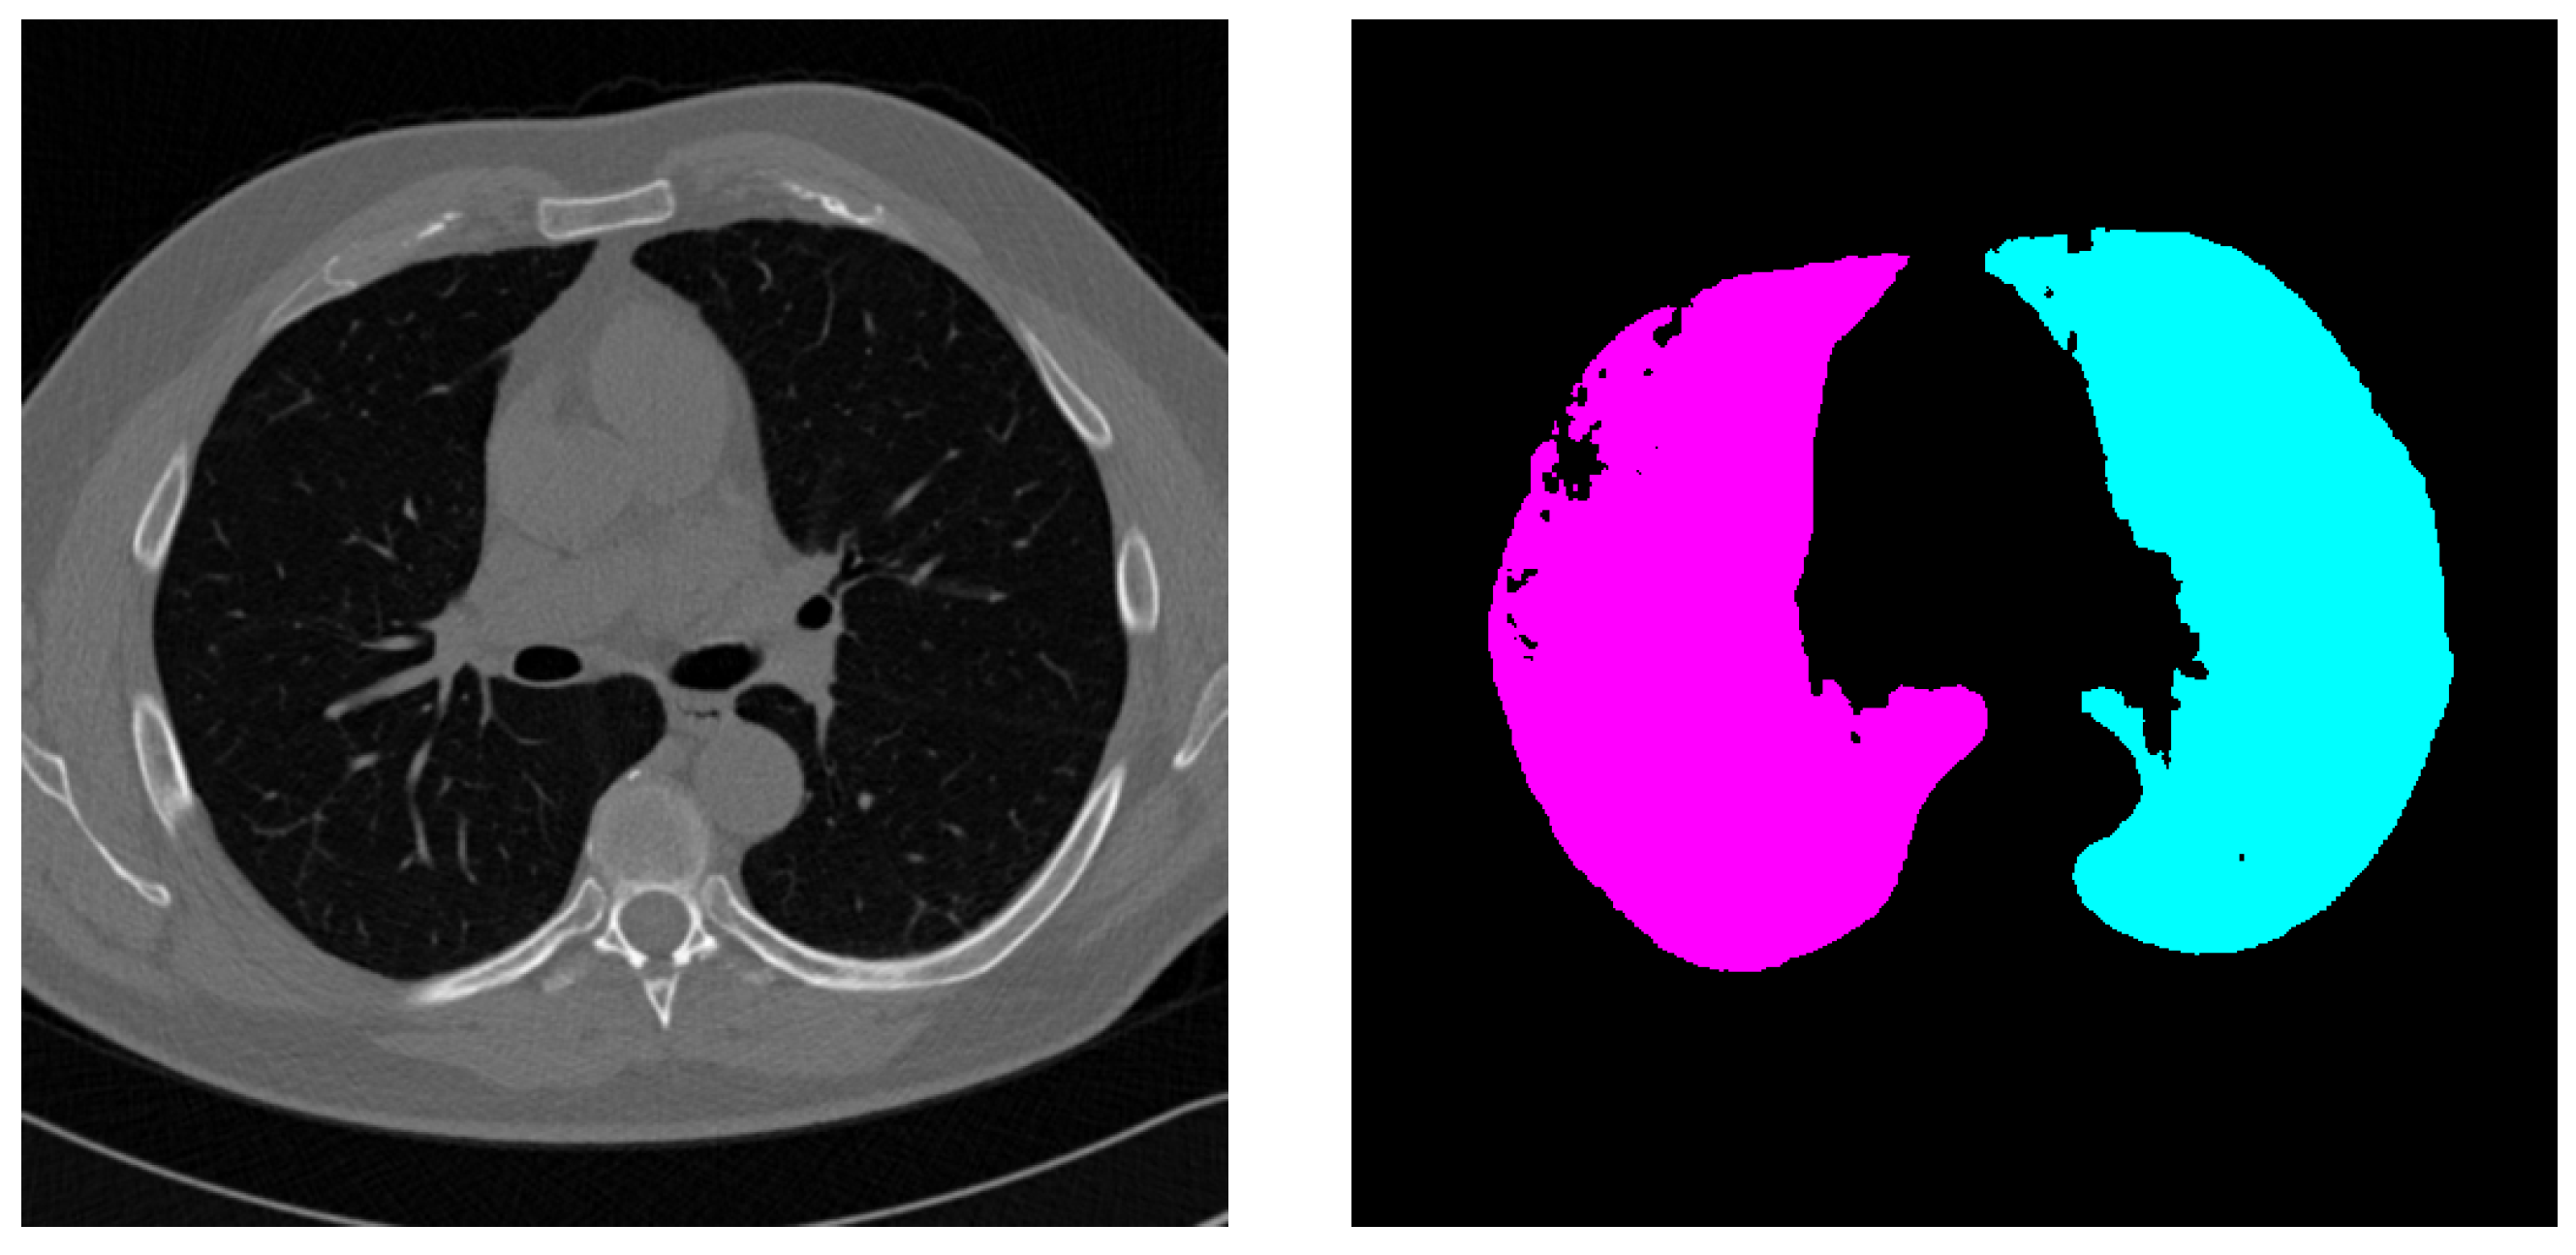

4.3. External Validation on PleThora Dataset

- Morphological Characteristics: The presence of anatomical structures with geometric characteristics similar to irregular or hidden ROI can generate segmentation errors. The model may incorrectly interpret these formations as potential ROI. In advanced lung disease, ROI such as tumors or affected lung parenchyma can exhibit highly irregular shapes and may be partially obscured or hidden by surrounding diseased tissue, pleural effusions, or consolidation, as frequently observed in the PleThora dataset. SALM, trained primarily on datasets with relatively well-defined ROI like LUNA16, may struggle to accurately delineate these highly irregular and poorly defined ROI in advanced pathological cases. The model’s reliance on shape features learned from less complex examples might lead to under-segmentation or inaccurate boundary delineation when confronted with the complex and atypical morphologies characteristic of advanced lung pathologies. This is further compounded by the fact that, in diseased lungs, the contrast between the ROI and the surrounding abnormal tissue may be reduced, making morphological differentiation even more challenging for the model.

- Positional Encoding Limitations: Overpredictions can result from an imperfect capture of three-dimensional spatial relationships, despite the use of modified positional encoding. Peripheral areas of anatomical structures, where intensity gradients are less pronounced, are particularly susceptible to misclassification. While our modified 3D positional encoding enhances spatial awareness, it is not perfect. In regions where anatomical structures are complex or boundaries are ill-defined, particularly at the periphery of organs or lesions where intensity transitions are gradual, the model might struggle to precisely delineate the ROI. This can lead to over-segmentation extending into surrounding tissues or misclassification of adjacent structures due to limitations in fully capturing the intricate 3D spatial context.